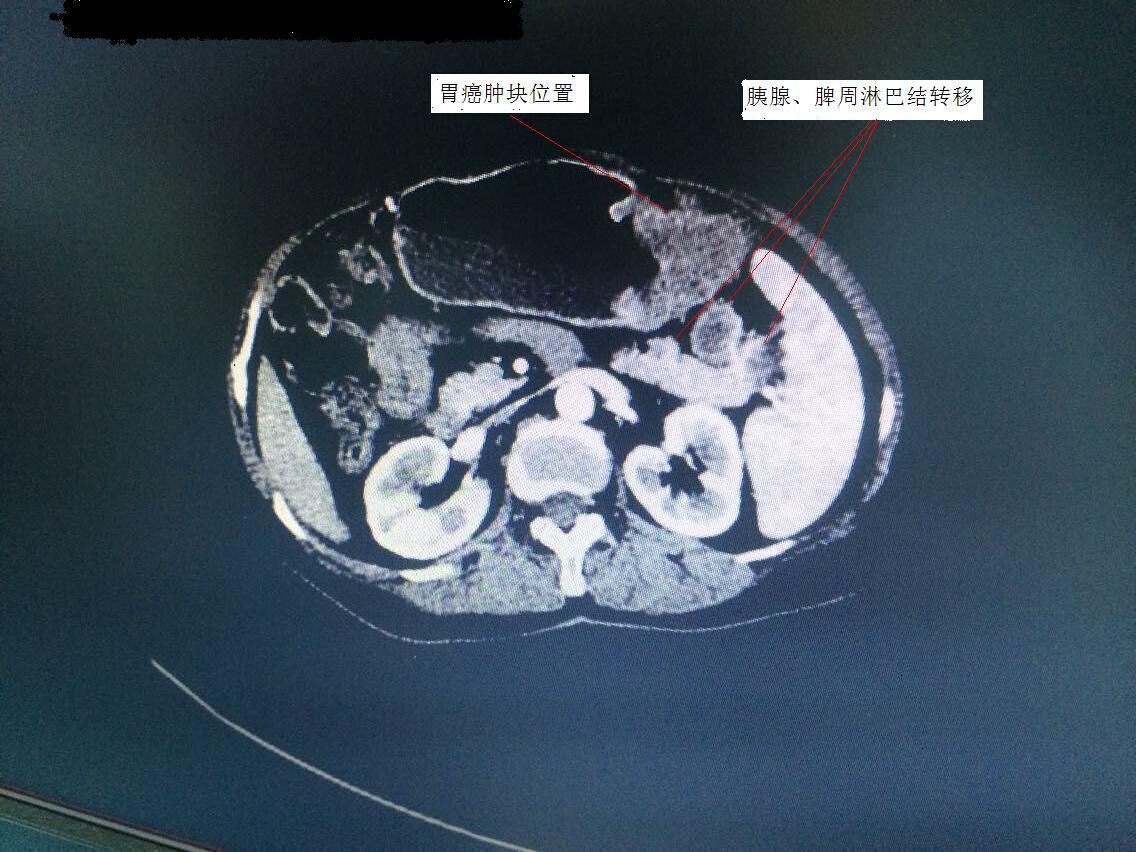

胃腸外科譚曙光主任率領(lǐng)科室團(tuán)隊(duì),術(shù)前對(duì)手術(shù)方案進(jìn)行了仔細(xì)研究。該患者胃癌腫塊位于胃體,腫塊較大,且胰腺尾部、脾門等周圍淋巴結(jié)轉(zhuǎn)移(見(jiàn)圖1)。為保證治療效果,提高患者生存質(zhì)量,需行全胃、胰腺體尾部以及脾臟聯(lián)合切除。此等手術(shù)在以往傳統(tǒng)開(kāi)腹方面均具有較高難度,若想在微創(chuàng)下完成切除,更是難上加難。經(jīng)過(guò)科室嚴(yán)密的探討,最終確定為該患者行腹腔鏡下微創(chuàng)手術(shù)。手術(shù)歷時(shí)3個(gè)小時(shí),在手術(shù)室及麻醉科的配合下,順利完成衡陽(yáng)市第一例腹腔鏡下胃癌根治聯(lián)合脾臟、胰腺體尾部切除術(shù)(術(shù)后標(biāo)本見(jiàn)圖2)。術(shù)后,該患者恢復(fù)良好,手術(shù)疤痕不到傳統(tǒng)手術(shù)的四分之一(見(jiàn)圖3),目前已開(kāi)始術(shù)后化療。

圖1